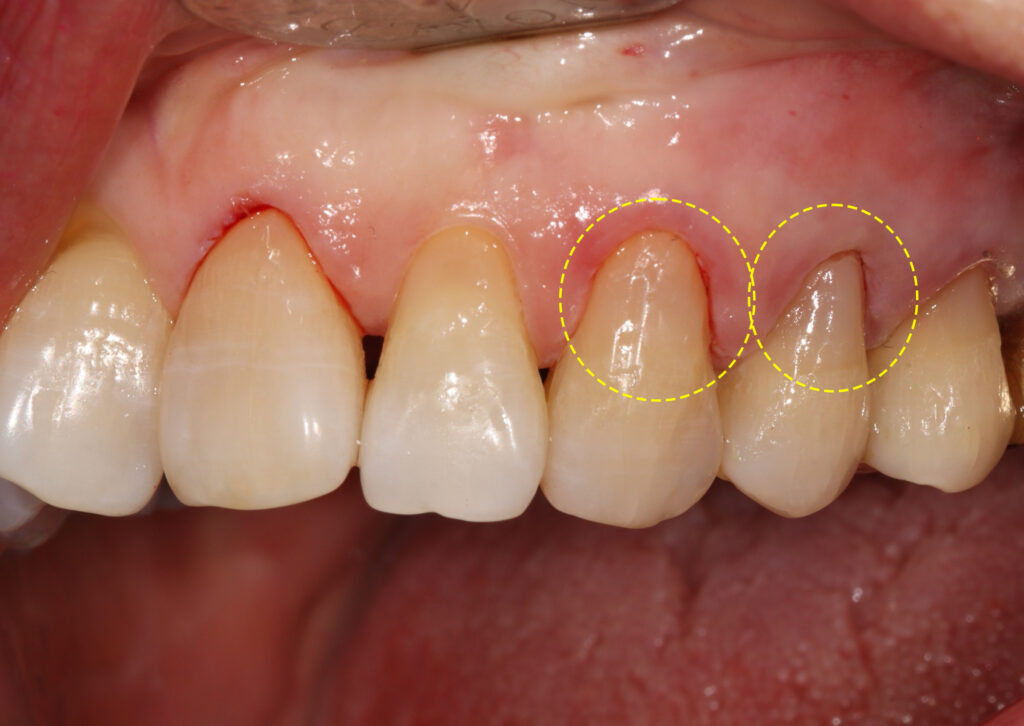

오늘 소개해 드릴 내용은 심하게 패인

치경부를 레진으로 수복하신 것을

사진을 보며 설명해 드리려고 합니다.

접착력과 마진 형성을 위해 잇몸에 실을 넣어

치은 압배를 진행한 모습인데요.

– 치경부 레진 주요 포인트

1. 치아면을 다듬어서 접착에 유리한 형태로 변화 시킴

2. 접착력을 높히기 위해 치은압배 후 수복

3. 시린 증상을 덜 유발하는 SE bond를 이용해서 접착력을 극대화

4. ** 플로우 레진과 패커플레진을 적절히 레이어링

5. 잇몸을 덮지 않도록 마진을 형성

치경부 수복 치료를 마친 모습입니다.